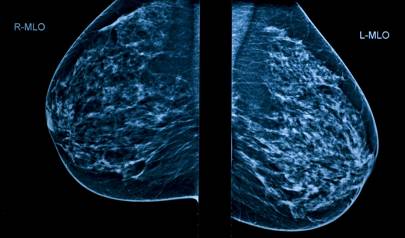

The AI software diagnoses cancer risk 30 times faster than a human doctor with 99 per cent accuracy

The AI program reliably interprets mammograms and translates patient data into diagnostic information 30 times faster than a human doctor, with 99 per cent accuracy.

The team used the AI software to evaluate mammograms and pathology reports of 500 breast cancer patients.

The software scanned patient charts, collected diagnostic features and correlated mammogram findings with breast cancer subtype. Clinicians used results, such the expression of tumour proteins, to accurately predict each patient's probability of breast cancer diagnosis.